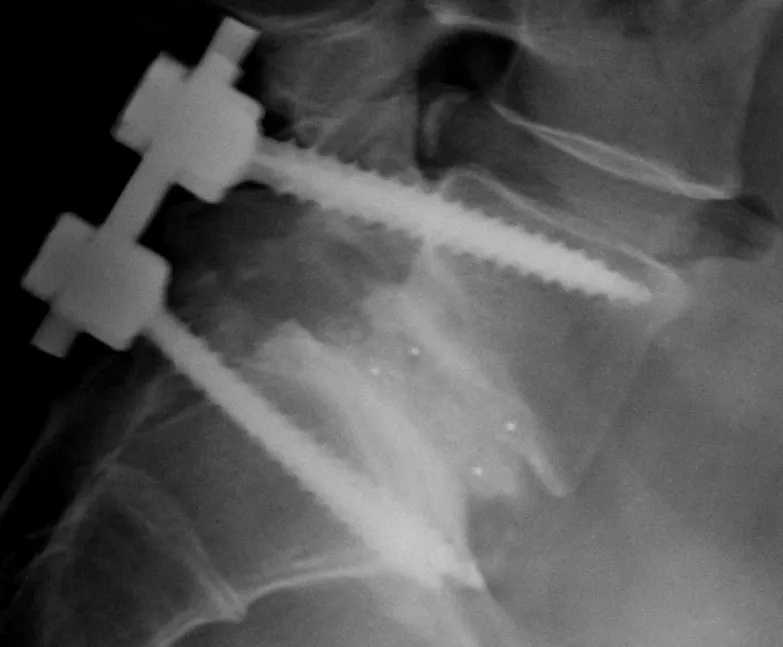

Спондилодез L5-S1, очень похожий на мой

Мой первый серьёзный момент «почему я / это несправедливо» произошёл, когда я был подростком. Врачи, после обследований, сказали, что мне срочно нужна спинальная фиксация. Где-то до операции мне внезапно вручили бумагу со списком вещей, которые я больше никогда не смогу делать в жизни.